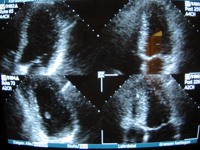

Stressechokardiografie

Bei einer Durchblutungsstörung der Herzkranzadern kommt es zu folgenden krankhaften

Abläufen: Sauerstoffmangel, Veränderungen im Energiestoffwechsel der Herzzelle, Störungen im Bereich der Zellwand mit Veränderungen des Mineraliendurchtritts, muskuläre

Störung der Herzwandbewegung, schließlich zu EKG-Veränderungen und ganz zuletzt zum typischen Schmerzereignis. So wird klar, dass der Arzt mit den gängigen

Untersuchungsverfahren (Ergometrie) oder der Patient mit seinen Beschwerden ganz am Ende der Ereigniskaskade steht. Hier setzt die Stressechokardiografie an. Mittels eines

speziellen Fahrradergometers (halbliegend und zur Seite kippbar) wird eine definierte Belastung des Herzens erzeugt. Über das Ultraschallbild lassen sich so auf der höchsten

Belastungsstufe frühzeitig Wandbewegungsstörungen lokalisieren. Die Bewegungssequenzen werden aus jeder Beschallungsebene und pro Belastungsstufe

digital als kleine Videosequenzen aufgezeichnet und bei der Auswertung gegeneinander verglichen. Die Sensibilität dieser Untersuchung für Durchblutungsstörungen der

Herzkranzadern ist gegenüber der Ergometrie deutlich gesteigert.

Die Stressechokardiographie wird von uns mit dem Philips HDI 5000 durchgeführt. Ein absolutes Spitzengerät,das durch zusätzliches

Harmonic Imaging eine unübertroffen gute Darstellung der Herzinnenhaut und damit der Wandbewegung erreicht.

digitalisierte Bilder werden ausgewertet: